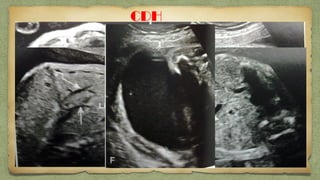

๏ƒผ CongenitalCongenital

DiaphragmaticDiaphragmatic

HerniationHerniation ::

fetal stomach may be absentfetal stomach may be absent

in an axial ultrasound scan โ€“in an axial ultrasound scan โ€“

standard view due tostandard view due to

migration into the thoraxmigration into the thorax